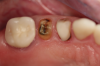

Fig 18. Preoperative image.

Figure 18